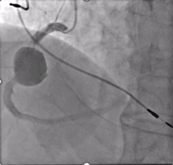

The authors present the successful percutaneous exclusion of a giant right coronary artery aneurysm in a patient with hypertension, dyslipidemia, and permanent atrial fibrillation.